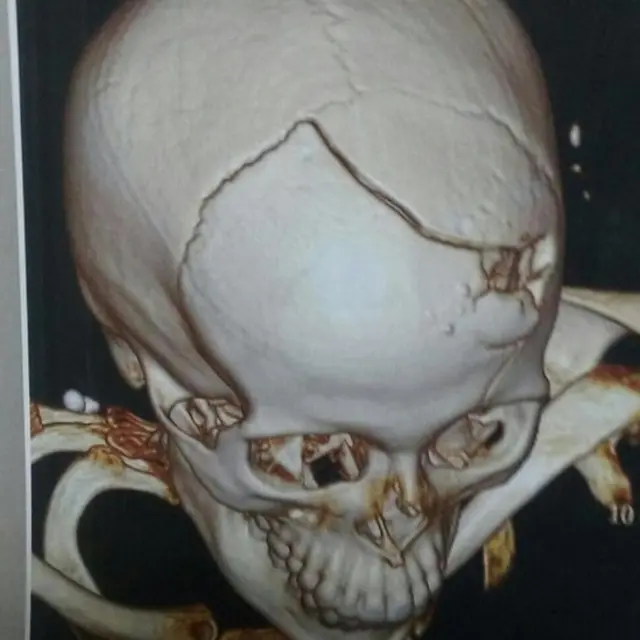

Su auto recibió seis disparos. Solo uno le pegó, en el hueso frontal del cráneo. El coche amarillo siguió varios metros, hasta chocar contra un muro verde.

Su madre cree que giró la cabeza justo cuando le disparaban y así la bala, que perdió fuerza al dar en el auto, fracturó su cráneo sin llegar a introducirse en él.

La socorrieron otros conductores que acababan de ser asaltados por la misma banda. En el hospital fue operada, en estado grave.

Cotta estuvo en coma inducido, en una unidad de tratamiento intensivo, hasta que comenzó a dar señales de mejoría. Siguió internada una decena de días y recibió el alta.

Su madre repite aliviada que no tendrá secuelas, de acuerdo a los médicos. Que ni siquiera le quedarán marcas visibles del balazo, gracias a una cirugía plástica.